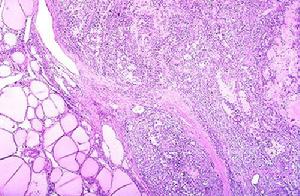

腎澱粉樣變性病理圖2.特殊治療